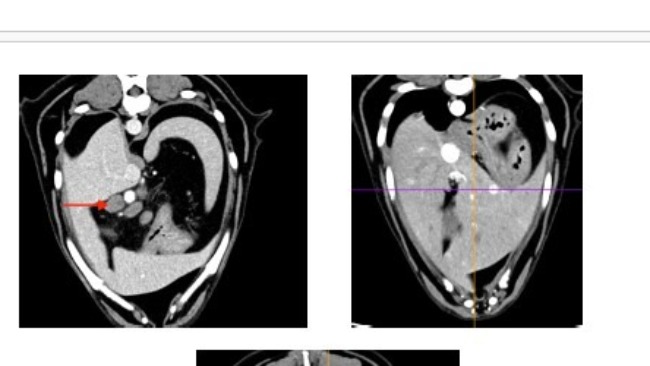

Wyniki badania biopsji guzów na śledzionie wykazały brak złośliwości.

Biopsja guzów na śledzionie

Wyniki badania krwi są stabilne. Płyny w jamie opłucnej są w śladowej ilości. Guz tym razem nie był widoczny na USG. Natomiast lekarz onkolog odkrył dwa guzy na śledzionie, które będą obserwowane i być może będą wymagały biopsji.

Na koniec roku same dobre wieści. Chłoniak jest w remisji. Lekarz onkolog zmniejszył ilość zaplanowanych cykli chemii z pięciu-sześciu do czterech.